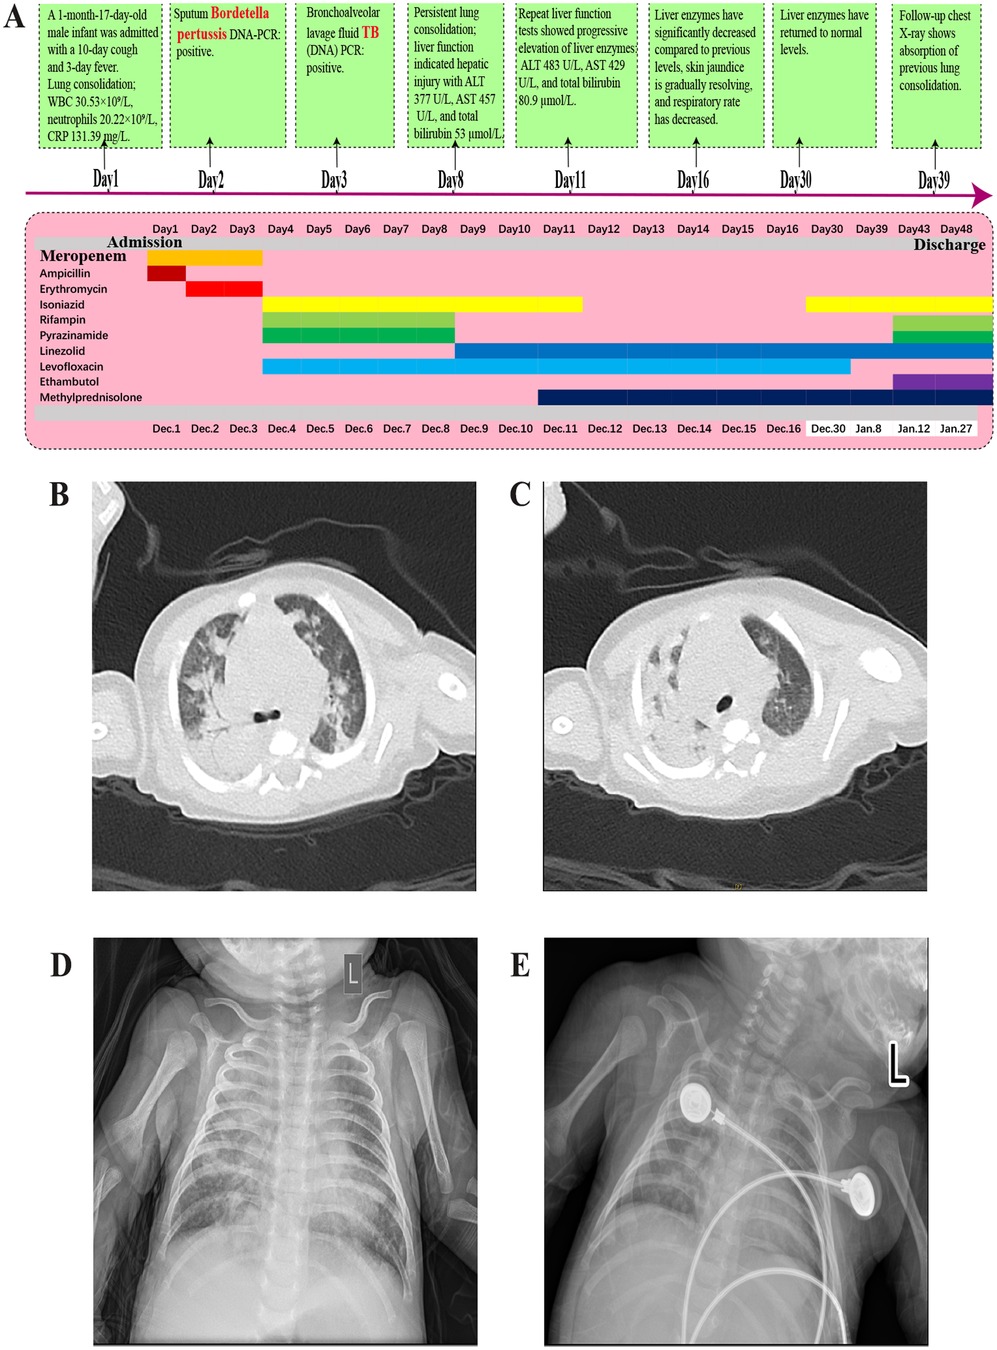

Background: Tuberculosis (TB) and pertussis are both highly contagious diseases caused by Mycobacterium tuberculosis (M. tuberculosis) and Bordetella pertussis (B. pertussis), respectively, with significant morbidity and mortality among children. However, neonatal co-infection with these two pathogens is extremely rare, and no such cases have been reported in the literature to date. Case Presentation: We reported a case of a 47-day-old full-term male infant admitted with cough and fever. Chest imaging revealed bilateral pulmonary consolidation. Bronchoalveolar lavage confirmed co-infection with M. tuberculosis and B. pertussis. Initial empirical antibiotic therapy was ineffective. Based on pathogen identification, treatment was adjusted to a combination of levofloxacin, isoniazid, rifampicin, and pyrazinamide. During treatment, the infant developed drug-induced liver injury, prompting several modifications to the anti-TB regimen, including the introduction of linezolid and adjunctive corticosteroids. With individualized therapeutic adjustments and close liver function monitoring, the infant's condition improved significantly, and he was eventually discharged in stable condition. Conclusion: This case underscores the importance of considering atypical pathogens in neonates presenting with severe unexplained pneumonia, particularly in regions endemic for TB and pertussis. Tailored antimicrobial strategies and dynamic assessment of drug toxicity, especially hepatotoxicity, are essential for successful management.